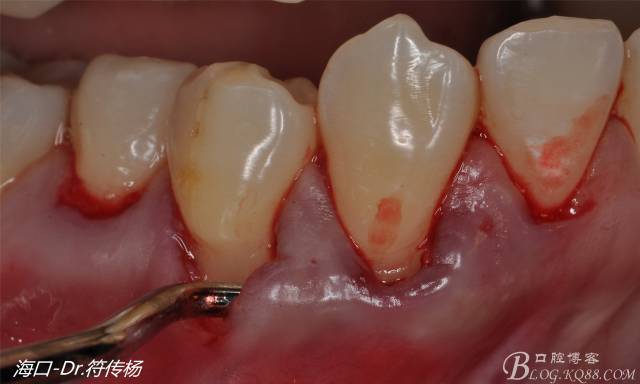

然后使用下頜開隧刀剝離牙齦

最后使用牙齦乳頭分離器分離牙齦乳頭